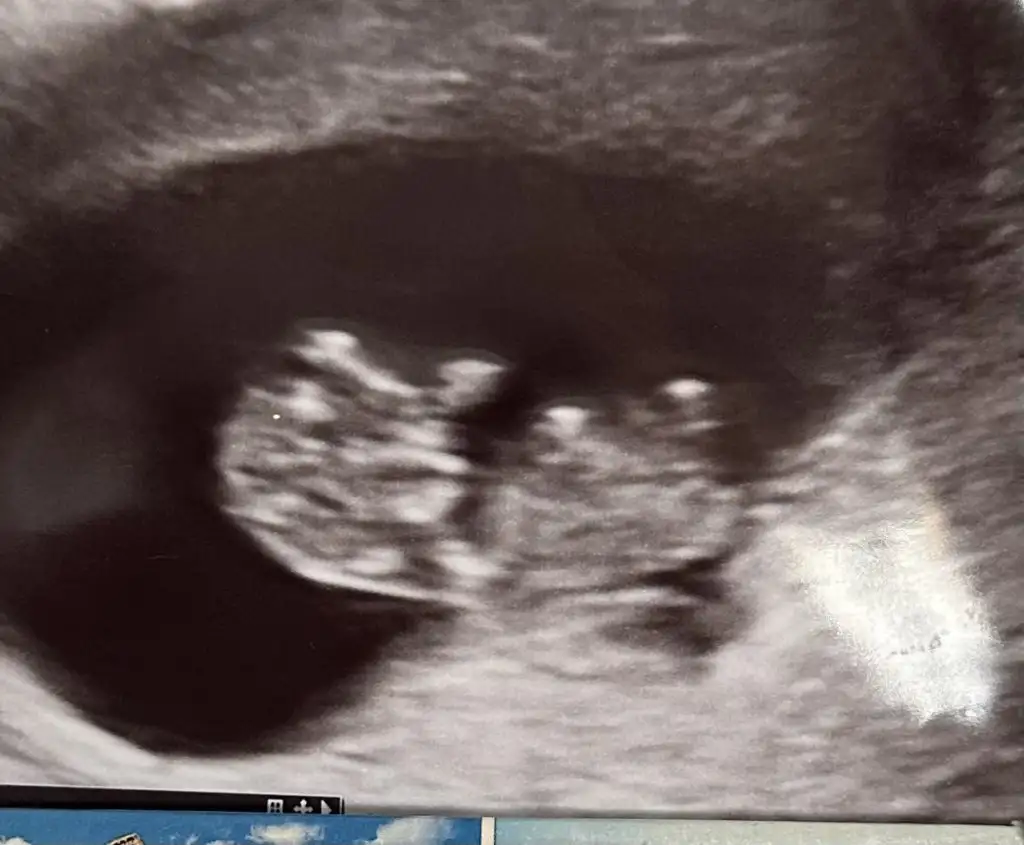

7 haftalik 1 oğlum 2 kızım var bu 4. Supriz bir bebek tahminde bulunurmusunuz

IMG_20240425_164730.webp